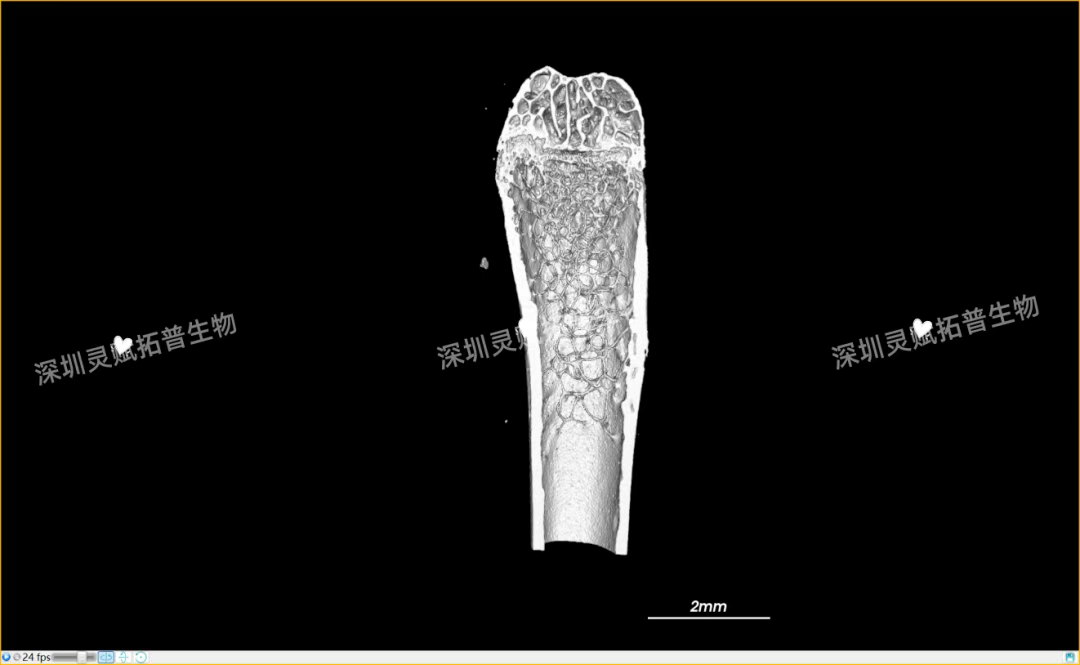

以小鼠股骨检测为代表,带大家直观感受sunbet中文官网生物的服务实力:

本次实验对 E2 系列(E2-1、E2-2、E2-3)共3个小鼠股骨样本进行标准化扫描,取得了 0.5mm、2mm 等不同尺度的清晰成像,不仅直观呈现了股骨的宏观形态,更精准捕捉到骨小梁排列、皮质骨厚度等微观细节,为后续骨质疏松、骨修复等相关研究给予了可靠的量化数据支撑。

下附E2系列的典型案例:小鼠股骨扫描成像图